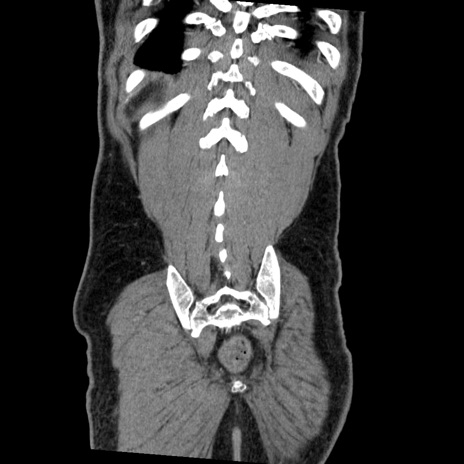

症例22(冠状断像)

【症例】50歳代男性

【主訴】腹痛

【現病歴】AVMからの被殻出血のため回復期リハ病棟入院中。 本日午後3時頃急に下腹部痛が出現した。

【既往歴】AVM、被殻出血、虫垂炎、高血圧

【身体所見】意識晴明、左半身不全麻痺、会話の理解は良好、36.5°C、腹部:膨隆、全体に板状硬、下腹部正中に圧痛点あり、反跳痛-、筋性防御不明、右下腹部にope scar

【データ】WBC 9400、CRP 0.06